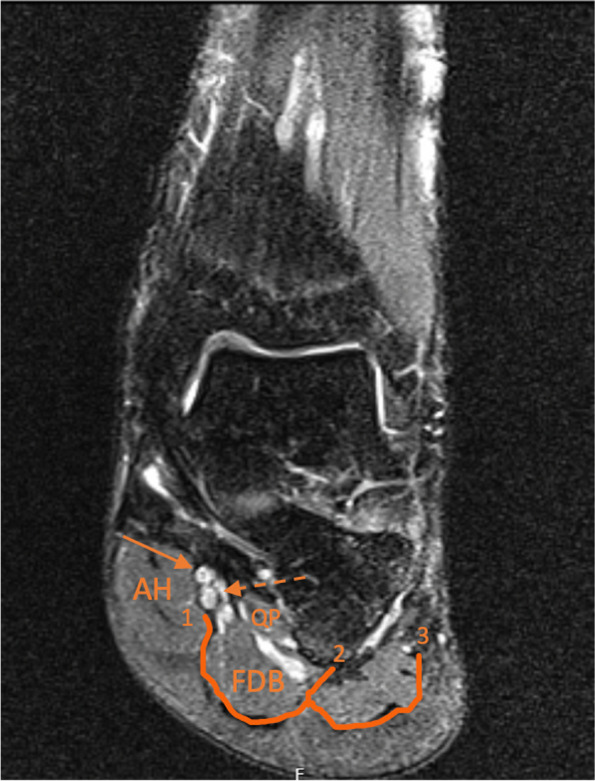

Methods: The distal part of the legs, ankles and feet of 12 Thiel embalmed cadavers were dissected. The pattern of the branches of the TN was registered and the measurements were performed according to the Dellon-McKinnon malleolar-calcaneal line (DML) and the Heimkes Triangle (HT).

Results: The TN divided proximal to DML in 87.5%, on top of the DML in 12,5% and distal in none of the feet. The Baxter's nerve (BN) originated proximally in 50%, on top of the DML in 12,5% and distally in 37.5% of the cases. There was a strong and significant correlation between the length of DML and the distance from the center of the medial malleolus (MM) to the lateral plantar nerve (LPN), medial plantar (MPN) nerve, BN and Medial Calcaneal Nerve (MCN) (ρ: 0.910, 0.866, 0.970 and 0.762 respectively, p <  0.001).